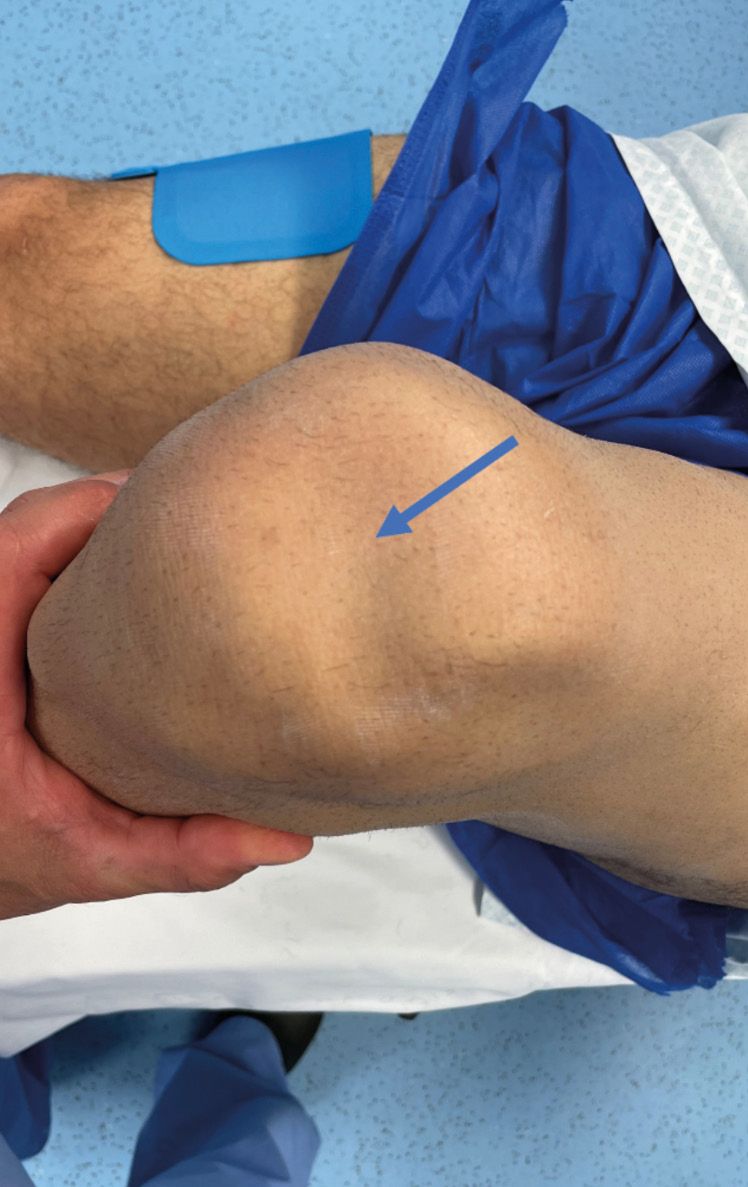

Patients usually describe a history of trauma involving eccentric contraction of the quadriceps and hyperflexion. Immediate after the event there is often haemarthrosis, a visible indentation above the patella (Fig. 1) and a loss of active extension.[9], Ilan DI, Tejwani N, Keschner M, Leibman M. Quadriceps tendon rupture. J Am Acad Orthop Surg. 2003;11(3):192-200. doi:10.5435/00124635-200305000-00006[19], Li PL. Acute bilateral rupture of the quadriceps tendon--an obvious diagnosis? Injury. 1994;25(3):191-192. doi:10.1016/0020-1383(94)90162-7[20], MacEachern AG, Plewes JL. Bilateral simultaneous spontaneous rupture of the quadriceps tendons. Five case reports and a review of the literature. J Bone Joint Surg Br. 1984;66(1):81-83. doi:10.1302/0301-620X.66B1.6693484[21] Kaneko K, DeMouy EH, Brunet ME, Benzian J. Radiographic diagnosis of quadriceps tendon rupture: analysis of diagnostic failure. J Emerg Med. 1994;12(2):225-229. doi:10.1016/0736-4679(94)90703-x

In chronic forms, patients commonly complain of anterior pain and instability when walking on sloped ground. A physical examination will reveal a loss of active extension and a indentation above the patella.